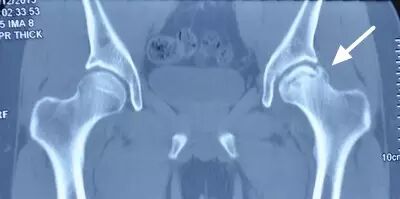

III期磁共振出现异常,X线片显示软骨下塌陷(新月征),股骨头内出现空洞,股骨头没有变扁

II期和III期的患者治疗方法相同,因为此时股骨头虽然还没有变形,暂时还不需要行人工关节置换术,但是股骨头已经出现空洞,随时股骨头就会塌陷变形,所以单纯的股骨头减压术是不能达到治疗效果的。这时就需要在股骨头减压的同时,植入一根支撑棒,顶住股骨头空洞区,防止股骨头在负重的情况下过早塌陷。其他治疗同之前相同,口服以上药物,定期复查,密切观察病情发展,尽量避免重体力劳动和爬山爬楼。

以上为股骨头坏死减压加支撑棒植入术示意图和术后X线片